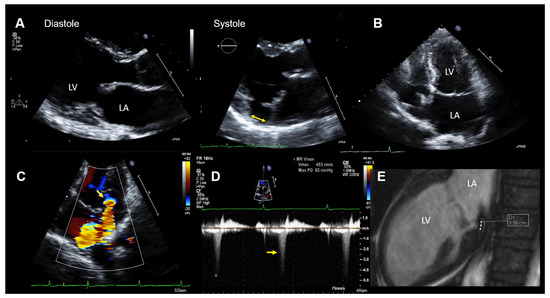

Figure 2.

Case 1: Summary of the key findings from multimodality imaging. (A) The mitral annular disjunction (MAD) (yellow double arrow) is only visible in systole in a parasternal long-axis transthoracic echocardiography (TTE) view. (B) A mildly enlarged left atrium is seen in a 4-chamber TTE view. The MAD is not clearly visualized. (C) The proximal isovelocity surface area (PISA) zone (yellow arrow) is seen. A PISA radius of 4 mm and a vena contracta of 3.5 mm indicated nonsevere mitral regurgitation (MR). (D) MR occurs only in the late-systole (yellow arrow) in Doppler imaging. (E) The MAD is measured in cardiac magnetic resonance imaging (white dots = 5.8 mm). LA = left atrium and LV = left ventricle.

When 2D TTE imaging is used, a MAD is assessed by measuring the distance from the site of the posterior leaflet insertion into the left atrial wall (upper border of the disjunction) to the connection between the left atrium and the ventricular myocardium (lower border of the disjunction). This should be performed in a parasternal long axis TTE view at end-systole (see, also, Figure 2A and Figure 3A). Carmo et al. found a MAD prevalence of 55% (21/38patients) in patients with MMVD and MVP examined by TTE [16].

At the hospital, a physical examination was normal other than mid-systolic click and a mid-late systolic murmur upon cardiac auscultation. The ECG showed no abnormalities, except for frequent polymorphic premature ventricular contractions (PVTs). The laboratory results were within the normal limits. A TTE demonstrated normal LV size and function. The mitral valve appeared myxomatous, and bi-leaflet MVP was present. MR was purely late-systolic (which confirmed the auscultation findings), and by the multimodal quantification of MR, it was moderate. In addition, a MAD was seen. The echocardiographic findings are summarized in Figure 2.

Coronary heart disease was excluded with computed tomography coronary angiography. Due to the aborted SCD and the frequent premature ventricular contractions (PVCs) on the ECG, as well as MAD with MVP, an electrophysiological study was performed, which showed inducible polymorphic ventricular tachycardia (VT).

CMR imaging confirmed the diagnosis of moderate MR (regurgitation fraction was 24%) with mild mitral annular dilation and the presence of a MAD (Figure 2E). The overall LVEF and right ventricular ejection fraction was normal, but a mild hypokinesis of the inferolateral wall was described. In addition, late-gadolinium enhancement CMR imaging showed an increased late-gadolinium uptake in the inferior and inferolateral walls consistent with focal myocardial fibrosis.